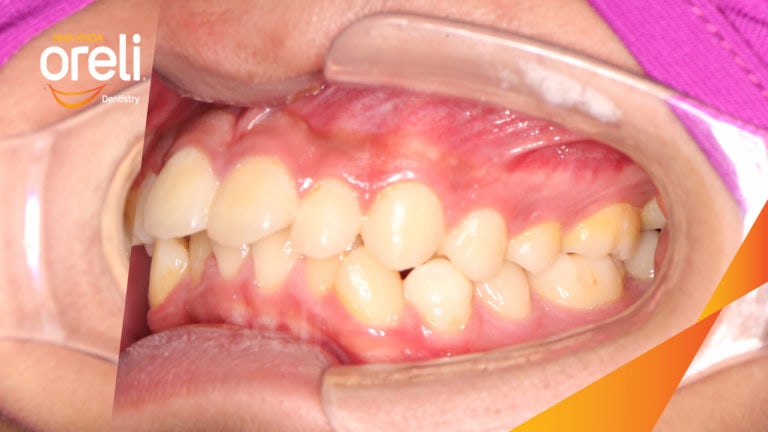

Ca niềng chỉnh cắn sâu hô lùi cằm cho kết quả nụ cười và góc nghiêng đẹp ở Oreli Niềng răngCắn sâuHôLùi cằm Xem thêm